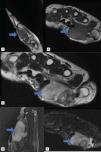

Se solicitaron radiografías simples (fig. 1), ecografía (fig. 2) y resonancia magnética (fig. 3).

La descripción ecográfica del TCGVT es una lesión hipoecoica, heterogénea, con Doppler, en relación con el tendón afectado. En resonancia se presenta como una lesión lobulada, de intensidad intermedia en T1 y T2, que en STIR muestran realce intenso. La determinación de focos de hemosiderina hipointensos es útil para diferenciar de otras lesiones.